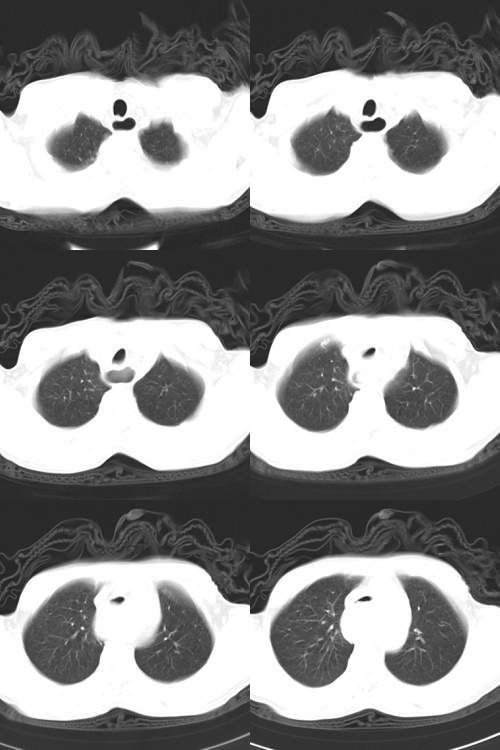

以下是引用zsl6918在2009-2-7 7:38:00的发言:[br]恶性度极高的肺癌,肺门及纵隔淋巴结转移。

以下是引用余辉在2009-2-7 8:29:00的发言:[br]考虑左下肺周围型肺癌伴肺门、纵隔淋巴转移及右肺转移